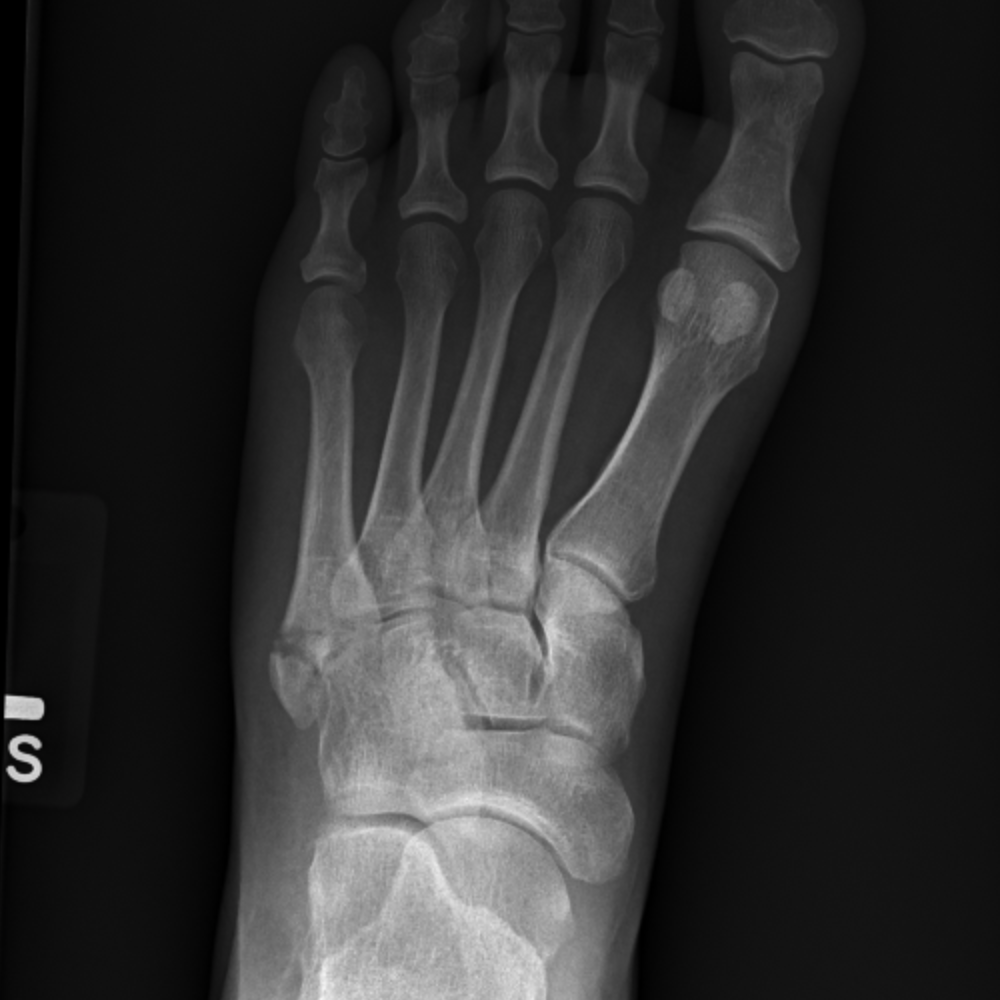

A calcaneal fracture is a break of the calcaneus (heel bone). Calcaneal fractures are often open and can be complicated by osteomyelitis, septic calcaneal bursitis, sequestration, and chronic drainage. It is a rare type of fracture but has potentially debilitating results.

A systematic evaluation of associated conditions. If a calcaneus injury is found, look for concomitant. Loading stack minimally displaced but slightly comminuted fracture of the anterior process calcaneus (arrows) with considerable overlying soft tissue swelling involving the subcutaneous tissues and bifurcate ligament. Comorbidities that preclude good surgical outcome (smoker, diabetes, pvd). • most intraarticular calcaneus fractures are the result of an axial load applied directly to the heel. Inversion with plantar flexion can lead to an avulsion fracture. A systematic evaluation of associated conditions. Fractures of the anterior process of the calcaneus occur following an acute injury to the foot. Symptoms may include pain, bruising, trouble walking, and deformity of the heel. J am podiatry assoc 1984;74(8): S92.021a displaced fracture anterior process right calcaneus, initial closed. Sclerotic line may be only evidence of impacted fracture. Answer | the anterior process of the calcaneus usually fractures due to an avulsion or traction injury. Calcaneal fractures are often open and can be complicated by osteomyelitis, septic calcaneal bursitis, sequestration, and chronic drainage. Anterior process fracture involving <25% of calcaneocuboid joint. Anterior process of calcaneus fracture. Fracture of anterior process of calcaneus.